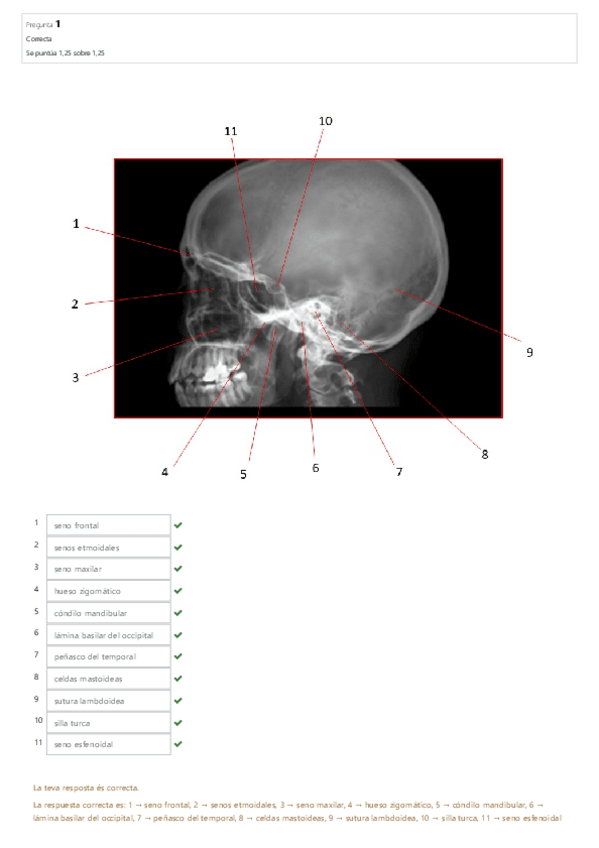

He publicado nuevos test de 1º Aparato Locomotor: CUESTIONARIO-CRANEO.pdf

8 páginas